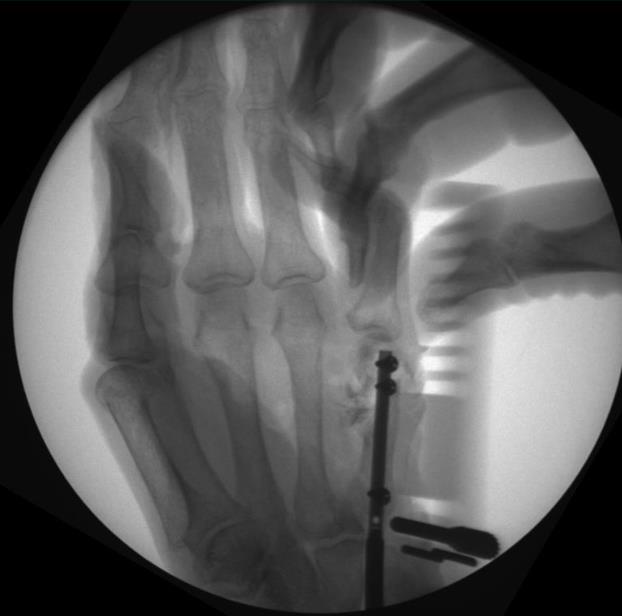

• confirm fracture reduction and final nail position with fluoroscopy, ensuring the locking screw holes are not near fracture lines

• confirm final reduction and implant position using fluoroscopy

• use fluoroscopy for fracture reduction, length determination, provisional fixation confirmation, screw placement confirmation, and final implant confirmation